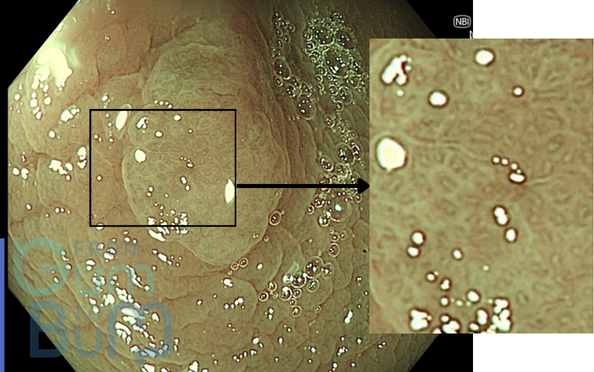

Which Kudo pit pattern does this lesion present?

Your paragraph text 11